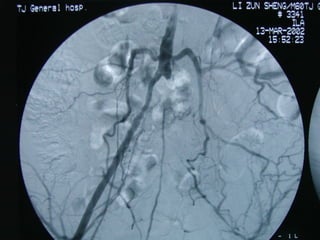

Endovascular therapy Percutaneous transluminal angiography(PTA)  The classic approach is to advance a guide (or a long sheath) across the stenosis over the previously placed guide wire; the vascular stent is then passed through the guide and positioned at the lesion, the guide is withdrawn, and the stent is deployed

Endovascular therapy Percutaneoustransluminal angiography(PTA) The classic approach is to advance a guide (or a long sheath) across the stenosis over the previously placed guide wire; the vascular stent is then passed through the guide and positioned at the lesion, the guide is withdrawn, and the stent is deployed